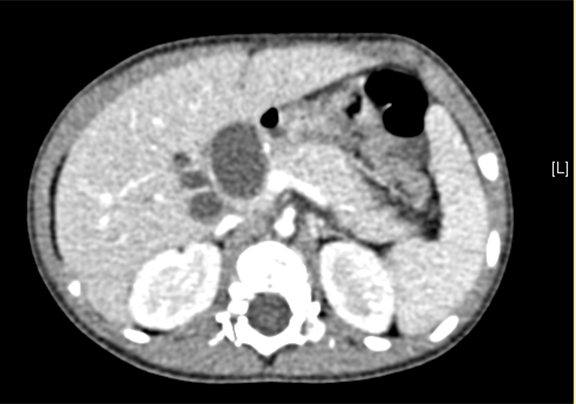

上腹部动态三维成像(增强)CT:诊断意见:符合胆总管囊肿胆囊炎可能性大。

术前CT检查:

静脉期